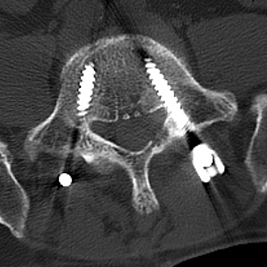

陈勇主任团队顺利为患者置入椎弓根螺钉。术后患者腰腿痛症状较术前明显缓解,肢体活动无障碍,术后3天即在脊柱支具外固定的辅助下下地行走,术后第7天患者恢复情况良好,顺利出院。

▲术中椎弓根螺钉精准置入

术后复查X线、CT

椎弓根螺钉内固定技术是目前脊柱手术中最常应用的固定技术,但在椎弓根置钉过程中存在损伤神经与血管的风险。提高置钉安全性及成功率一直是脊柱外科医师研究的重要内容。